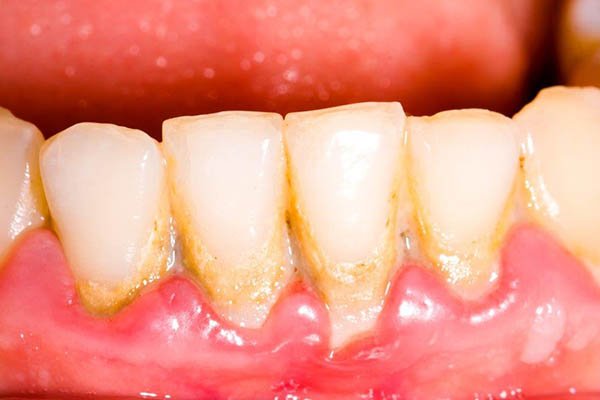

No aspecto local, a má higiene oral e o consequente acúmulo de biofilme dental e cálculo criam um microambiente anaeróbio que potencializa a proliferação de microrganismos agressivos.

O sinal mais marcante é a necrose das papilas interdentais, frequentemente descrita como uma aparência em “cratera”, resultado da destruição tecidual localizada. Sobre essas áreas necrosadas, observa-se a formação de pseudomembranas acinzentadas ou esbranquiçadas, que recobrem as lesões e podem ser facilmente removidas, revelando um tecido subjacente intensamente dolorido e sangrante.

- Remoção mecânica suave da placa e cálculo supragengival, evitando traumatizar os tecidos.